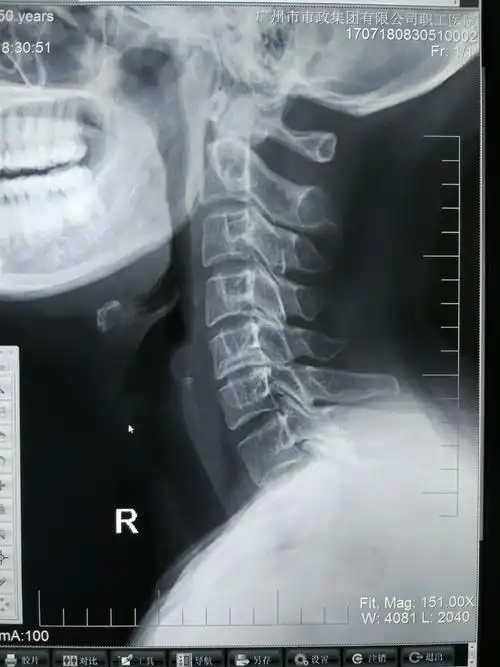

市第一院骨二科成功救治一例高位颈椎骨折并完全脱位患者获得成功

一例高位颈椎脱位并不全瘫患者的救治经过

寰椎的位置和其与其它颈椎的位置没有明显的错位征.